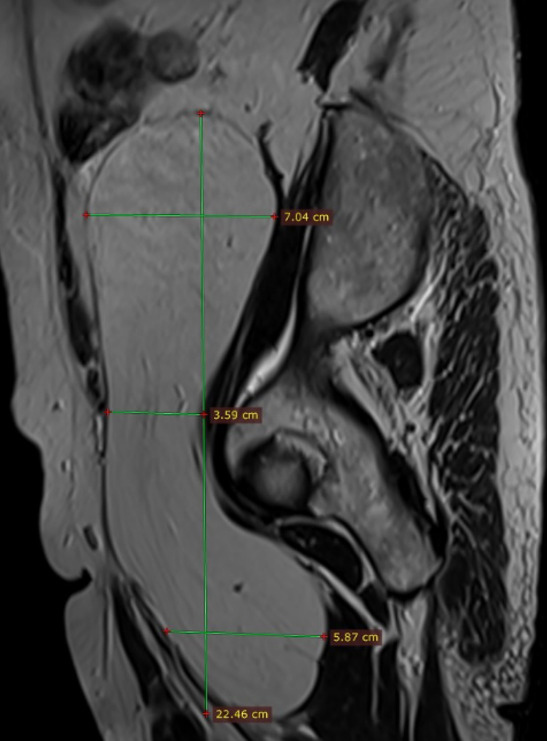

Asymptomatic Retroperitoneal Lipoma with Extension to the Right Anteromedial Thigh

2. Case Presentation